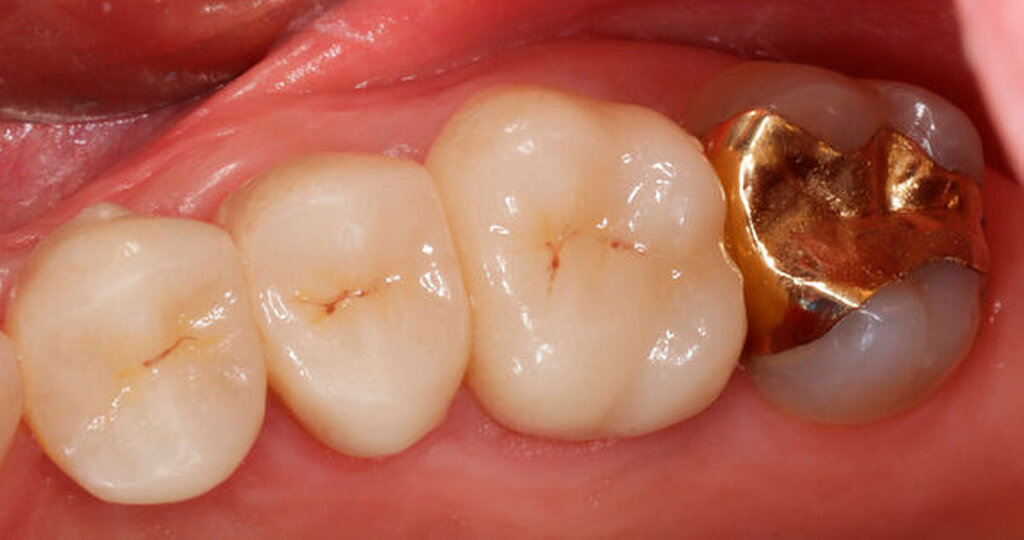

Nach der Wurzelamputation erfolgte in allen hier dargestellten Fällen nach etwa vier Wochen Ausheilzeit die prothetische Versorgung der Zähne mit Einzelkronen.

Im Rahmen der Versorgung erfolgte auch ein Austausch der Extensionsbrücke 16–14 durch Einzelkronen auf 16 und 15 sowie einer Implantatversorgung mit Einzelkrone in Regio 014. Der Erhalt des Zahnes 16 ermöglichte so eine wenig invasive Versorgung des ersten Quadranten mit guter Hygienefähigkeit. Alternativ wäre bei Extraktion des Zahnes die Versorgung beispielsweise mit einer ausgedehnten Brückenkonstruktion von 13–17 oder einem weiteren Implantat in Regio 016, vermutlich mit (indirektem) Sinuslift, notwendig gewesen. So konnte der Fall minimalinvasiv zufriedenstellend gelöst werden. Die Patientin ist seit dem Eingriff beschwerdefrei und kommt gut zurecht. Die Situation ist nun seit sechs Jahren stabil.

So folgte nach der Wurzelfüllung die Amputation der mesiobukkalen Wurzel. Der Zahn wurde nach der Amputation auf Wunsch der Patientin zunächst mit einem Langzeitprovisorium versorgt, das im Verlauf gegen eine definitive Versorgung ausgewechselt wurde. Die Patientin ist seitdem an 16 beschwerdefrei, der Zahn ist stabil und hat eine gute Langzeitprognose.